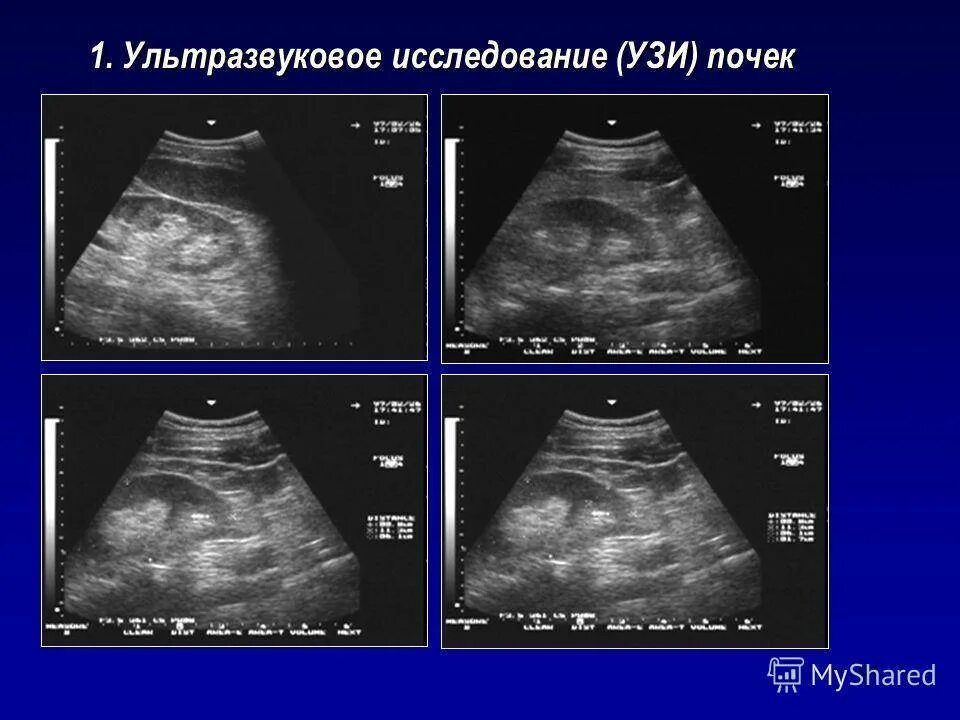

Узи сердца узи почек